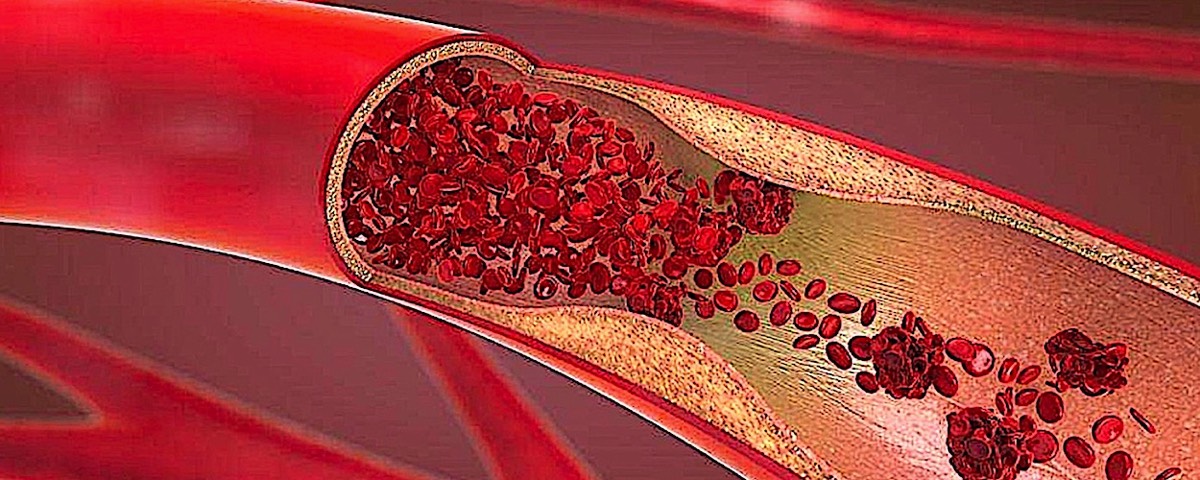

💥Info Blood Circulation💥

Your circulatory system, or cardiovascular system, supplies oxygen and nutrients to your whole body and removes waste through your blood. Your heart pumps blood that flows through your arteries, veins and capillaries. These blood vessels and your heart form your circulatory system. They work together to ensure your cells have what they need.

💥Improve Blood Circulation💥

If you lack good blood flow, your body is missing out on essential nutrients and oxygen. Improve blood circulation to improve vein health. If you don’t, varicose veins and leg swelling are some of the symptoms you are risking. Here are a few tips that you can try to improve your circulation and the health of your heart.